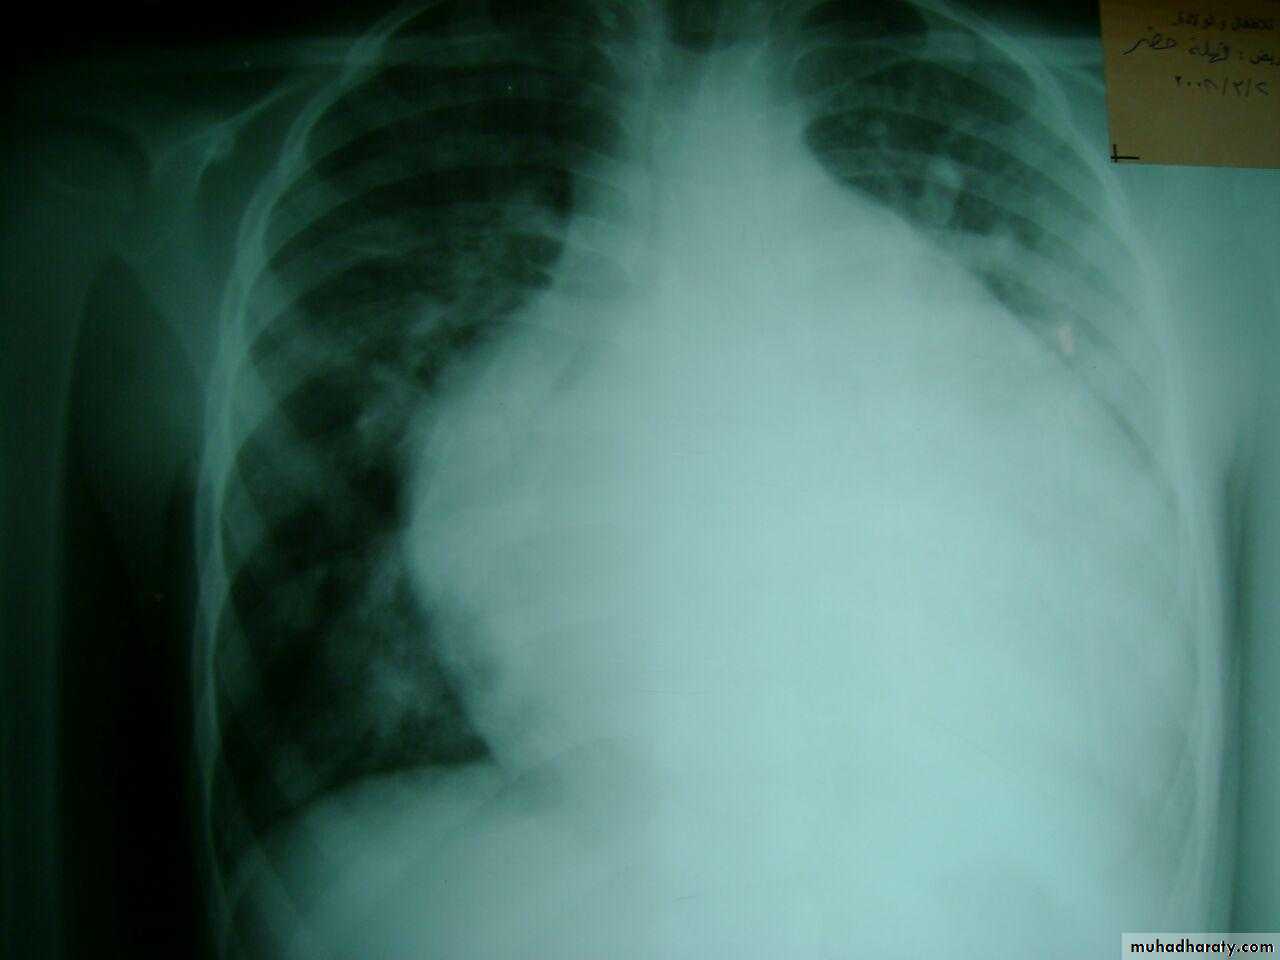

pleural effusion - multiple opacities

TB ddxheart cardiomegaly و pleural effusion

May with periphral lymph adenopathyNormal ECG

TBPleural effusion meniscal sign